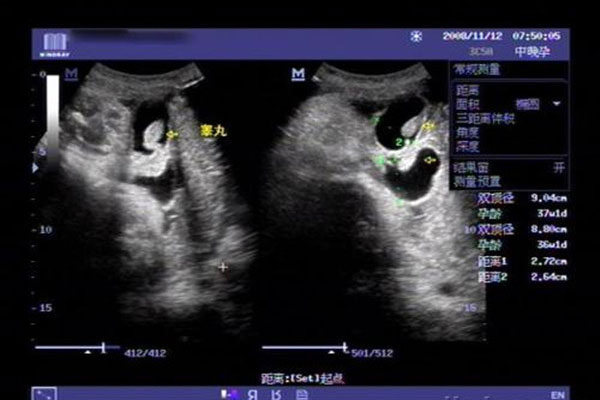

孕26周四维下睾丸的样子 如何看四维彩超识性别呢?

四维彩超,相信很多妈妈都是熟悉的,特别是孕妈妈们都是做过四维彩超的,它与普通B超不同,是非常先进的排畸仪器设备。好友珊珊怀孕刚好26周,前些日子陪着一起去做四维彩..